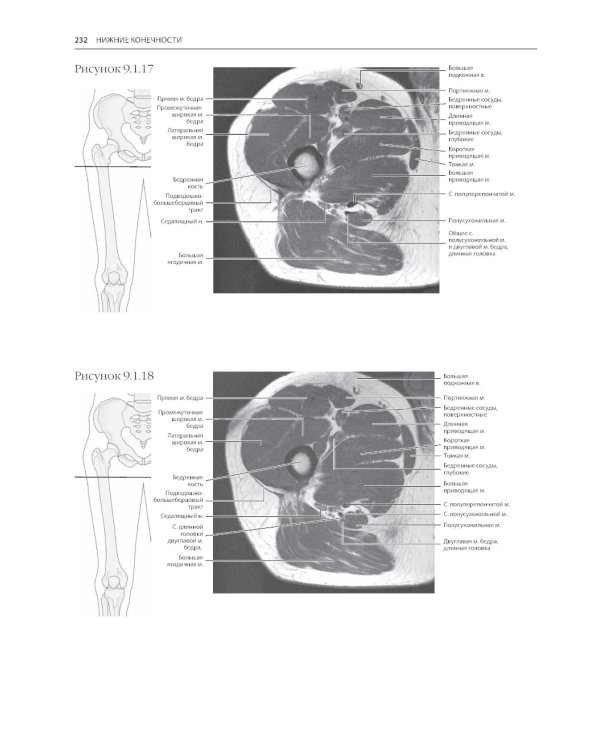

Четвертое издание лучшей книги по секционной анатомии для специалистов в области компьютерной томографии и магнитно-резонансной томографии. Более 1000 иллюстраций высочайшего качества и подробные обозначения позволяют получить полное представление о возможностях современной визуализации верхних и нижних конечностей, органов грудной клетки, брюшной полости и малого таза. Помимо классических ортогональных проекций КТ и МРТ приведены последовательные томограммы, полученные в наиболее значимых в клинической практике тангенциальных проекциях.